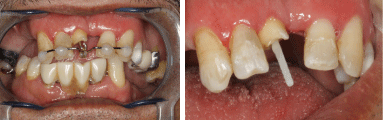

The patient is an 65 year old man without systemic problems with a fractured crown of tooth number 8. The patient stated that he had a motorcycle accident about 3 months ago and he suffered from this fractured tooth due to impaction and severe pain.He had RCT treatment 9 weeks ago,but after the pain subsided, he did not return for further treatment due to his economic problems. He had visited several centers for treatment in the last few days, but he had not achieved any results, and finally, due to deep decay in mesial and distal, he was advised to extract the tooth. When he was clinically examined in Restorative Dentistry Department of Tehran University of Medical Sciences, the RCT treatment was assessed and the decay was entered into the coronally aspect of the root. The deepest carious area was located approximately 2 mm below themesial bone crest, so during crown lengthening surgery, at least 5 mm of bone had to be removed from this area to reach the minimum acceptable amount of healthy tooth tissue, excluding the bone from the mesial side of tooth number 8 (Figure 1). This procedure required extensive osteectomy on adjacent teeth, and performing it on the central teeth of the upper jaw would have created significant cosmetic problems for the patient. Considering the mentioned problems, the patient's age and, the best cost effective choice in this case was forced eruption.

Figure 1: Tooth number 8 at first visit of 65years old patient. View Figure 1